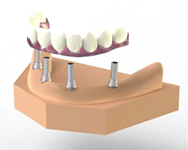

Pevné můstky – lepené nebo šroubované

Pevné můstky – lepené nebo šroubované

Metoda All-on-four

Metoda All-on-four

Bezzubá čelist je hlavní indikací pro ošetření pomocí implantátů. Zejména celkové zubní náhrady v dolní čelisti mají velice nízkou stabilitu a držení díky velkému úbytku kosti.

S pomocí zubních implantátů můžeme díky různým kotevním systémům (třmeny, kulové hlavy, Locatory) zajistit stabilitu a držení protézy nebo při použití většího počtu implantátů zhotovit pevné náhrady – můstky nalepené nebo našroubované na pevno na implantáty.

S těmito typy náhrad můžeme dosáhnout perfektní funkci, výbornou estetiku, fonetiku a současně zajistit u pacienta možnost dobré hygienickou péče a čištění, která je pro životnost implantátů velice důležitá.